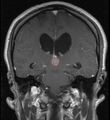

في كثير من الأحيان ، يُعرف شلل الحملقة إالعلوي جنبًا إلى جنب مع العديد من الموجودات العينية مثل رأرأة تراجع التقارب وتراجع الجفن المعروف أيضًا باسم علامة كولير وانفصال الضوء القريب (تتكيف الحدقة مع الضوء ولكنها لا تتفاعل مع الضوء) يسموا كمجموعة بمتلازمة بارينو[1] أو متلازمة الدماغ المتوسط الظهرية ، هي الأعراض الجسدية الوحيدة التي تظهر. يحدث هذا بسبب ضغط مركز الحملقة العمودي في سقف الدماغ المتوسط على مستوى الأكيمة العلوية والعصب القحفي III. يتضمن العمل عادةً التصوير العصبي كما يظهر على اليمين.[بحاجة لمصدر]